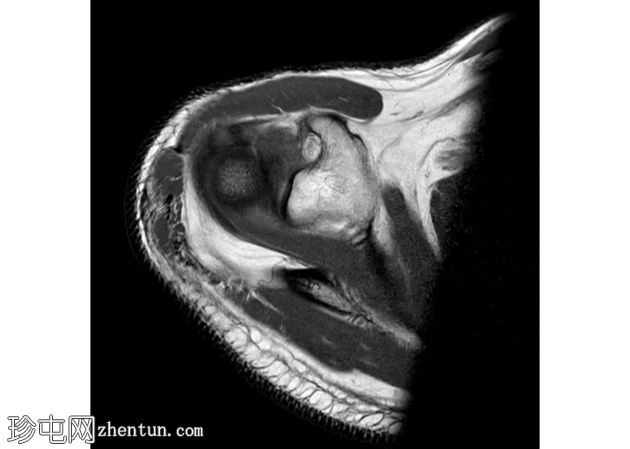

矢状面

PD 脂肪饱和度

肩袖分层撕裂通常被描述为肌腱物质的水平分裂。

其特征性表现是充满液体的裂隙,将关节面和滑囊肌腱层分开,形成“双层”外观。

关节面保持大致连续,而滑囊面不连续且回缩。分层会严重损害肌腱的生物力学。

这通常与外在撞击、骨刺和重复性过顶运动(例如投掷运动员、画家、游泳运动员)有关。